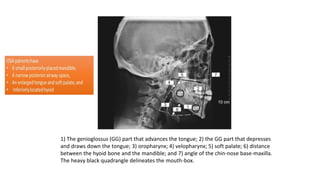

1) The genioglossus (GG) part that advances the tongue; 2) the GG part that depresses

and draws down the tongue; 3) oropharynx; 4) velopharynx; 5) soft palate; 6) distance

between the hyoid bone and the mandible; and 7) angle of the chin-nose base-maxilla.

The heavy black quadrangle delineates the mouth-box.

1) The genioglossus(GG) part that advances the tongue; 2) the GG part that depresses and draws down the tongue; 3) oropharynx; 4) velopharynx; 5) soft palate; 6) distance between the hyoid bone and the mandible; and 7) angle of the chin-nose base-maxilla. The heavy black quadrangle delineates the mouth-box.